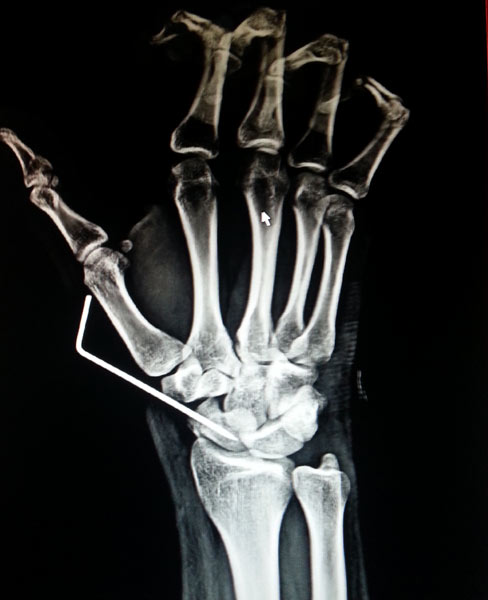

The young, male patient had the fracture of Rt scaphoid/ due to falling on an outstretched hand. The scaphoid fracture was treated, with the plaster cast for 1 ½ month elsewhere. Fracture of Rt Scaphoid was not united. This condition is called, the scaphoid non-union. It was treated with open reduction, and the iliac crest, bone grafting, and K wire stabilization.

During Surgery